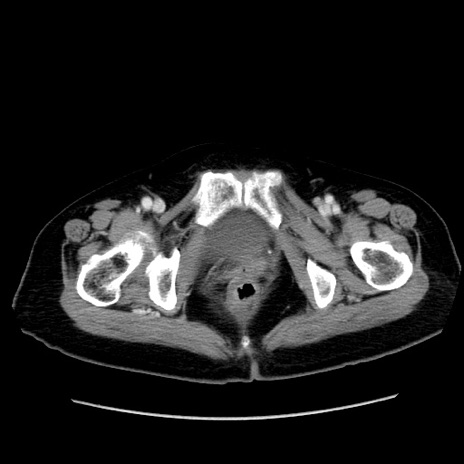

症例19(横断像)

【症例】80歳代女性

【主訴】下腹部痛

【現病歴】約8時間前より下腹部痛の出現あり、救急外来受診。

【既往歴】両側付属器切除

【身体所見】意識清明、下腹部正中に手術痕あり、その部位に一致して圧痛と反跳痛あり。腸蠕動音は亢進。

【データ】WBC 9300、CRP 0.15